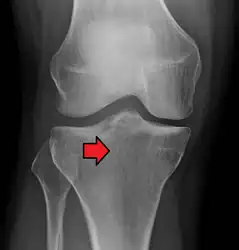

Subtle tibial plateau fracture on an AP X ray of the knee